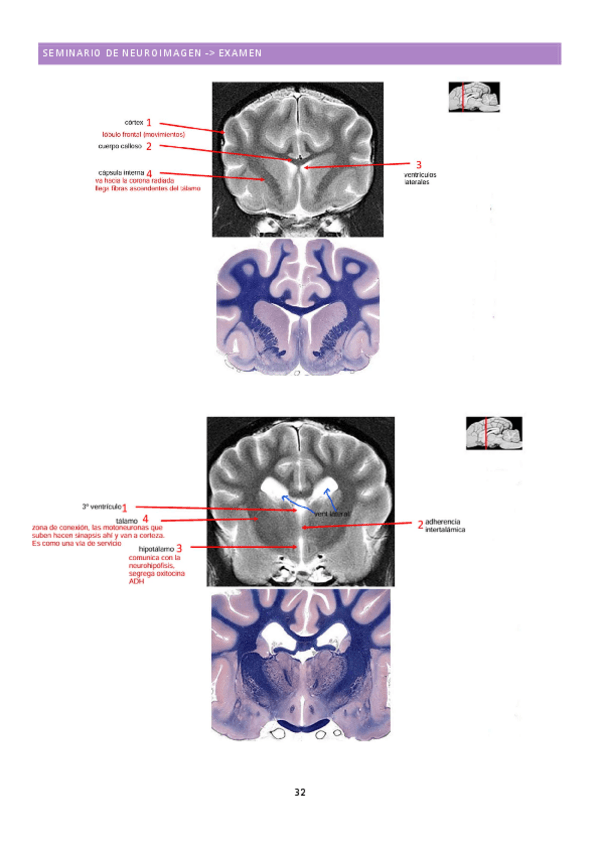

Seminario-neuroimagen.pdf

Respuestas del seminario de neuroimagen